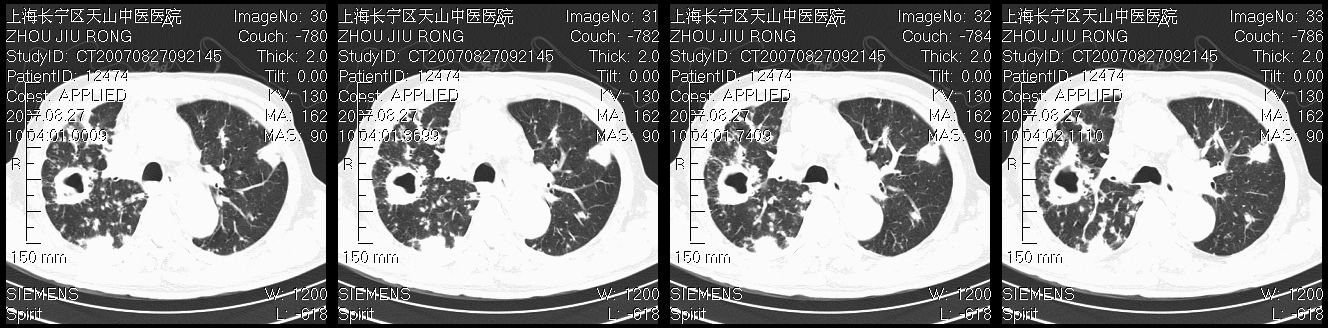

以下是引用zjzjr在2007-8-30 21:47:00的发言:[br]双肺弥漫性结节状、斑片状影,部分形成空洞,病灶以双肺上叶为著(符合结核发病部位),纵隔内见肿大淋巴结影。支持双肺继发性结核伴右上肺空洞形成。

以下是引用zjzjr在2007-8-30 21:47:00的发言:[br]双肺弥漫性结节状、斑片状影,部分形成空洞,病灶以双肺上叶为著(符合结核发病部位),纵隔内见肿大淋巴结影。支持双肺继发性结核伴右上肺空洞形成。

以下是引用gaoshengjiang在2007-8-31 10:24:00的发言:[br]双肺弥漫性斑片状影及多发空洞影,其间夹杂多量条索状影,胸膜肥厚、粘连并有结节状改变,纵隔多枚淋巴结肿大,考虑1双肺继发型肺结核合并感染?2韦格氏肉芽肿?[br] 支持!

以下是引用zjzjr在2007-8-30 21:47:00的发言:[br]双肺弥漫性结节状、斑片状影,部分形成空洞,病灶以双肺上叶为著(符合结核发病部位),纵隔内见肿大淋巴结影。支持双肺继发性结核伴右上肺空洞形成。

以下是引用zjzjr在2007-8-30 21:47:00的发言:[br]双肺弥漫性结节状、斑片状影,部分形成空洞,病灶以双肺上叶为著(符合结核发病部位),纵隔内见肿大淋巴结影。支持双肺继发性结核伴右上肺空洞形成。

以下是引用zjzjr在2007-8-30 21:47:00的发言:[br]双肺弥漫性结节状、斑片状影,部分形成空洞,病灶以双肺上叶为著(符合结核发病部位),纵隔内见肿大淋巴结影。支持双肺继发性结核伴右上肺空洞形成。